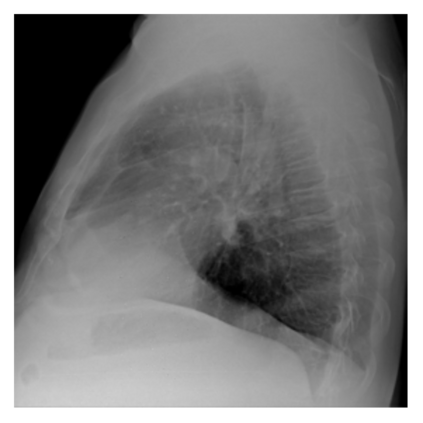

The evaluation of infectious disease processes on radiologic images is an important and challenging task in medical image analysis. Pulmonary infections can often be best imaged and evaluated through computed tomography (CT) scans, which are often not available in low-resource environments and difficult to obtain for critically ill patients. On the other hand, X-ray, a different type of imaging procedure, is inexpensive, often available at the bedside and more widely available, but offers a simpler, two dimensional image. We show that by relying on a model that learns to generate CT images from X-rays synthetically, we can improve the automatic disease classification accuracy and provide clinicians with a different look at the pulmonary disease process. Specifically, we investigate Tuberculosis (TB), a deadly bacterial infectious disease that predominantly affects the lungs, but also other organ systems. We show that relying on synthetically generated CT improves TB identification by 7.50% and distinguishes TB properties up to 12.16% better than the X-ray baseline.